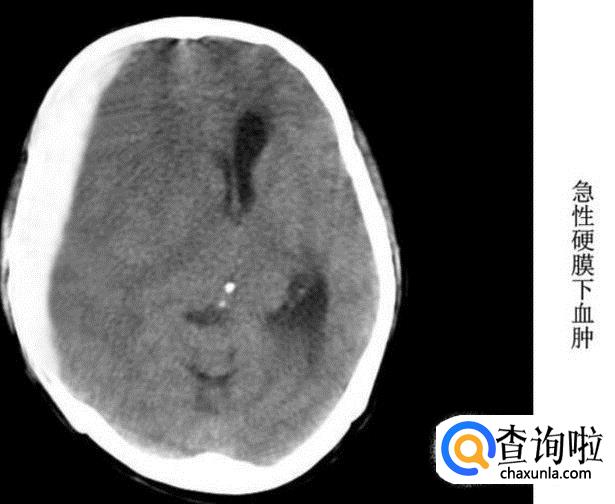

硬膜下血肿

急性硬膜下血肿:颅骨内板下新月形高密度,常伴脑挫伤,占位效应明显。

亚急性硬膜下血肿:呈新月形或半月形,血肿密度呈高密度或等密度。

慢性硬膜下血肿:高、低混杂密度,最后变为低密度直至消失。